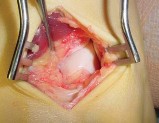

Question 5:

A 32-year-old female presents with progressive knee pain. Imaging reveals an eccentric, lytic, epiphyseal lesion in the proximal tibia extending to the subchondral bone without a sclerotic margin. Biopsy confirms multinucleated giant cells intermixed with mononuclear stromal cells. If targeted medical therapy is initiated prior to surgical curettage, what is the primary mechanism of action of the preferred agent?

Correct Answer: Monoclonal antibody binding to RANK ligand (RANKL)

The clinical and radiographic presentation is classic for a Giant Cell Tumor (GCT) of bone. Denosumab is a monoclonal antibody frequently used as neoadjuvant or primary medical therapy for aggressive or unresectable GCTs. It binds specifically to RANKL, preventing it from interacting with RANK receptors on osteoclast precursors and the giant cells themselves, thereby profoundly inhibiting osteoclastogenesis and tumor-associated bone destruction.